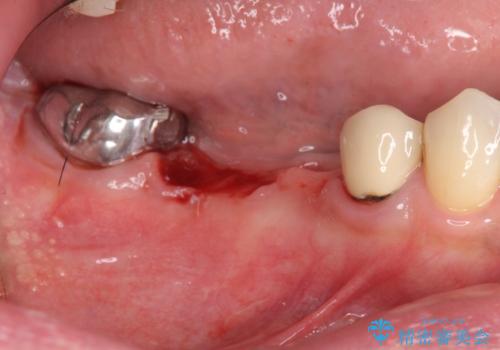

- 右下に入れた長いブリッジが噛むといたみ、改善を希望され来院されました。

長いブリッジは支台となる歯の過大な負担となることが多く、歯の破折や揺れ・痛みの原因となり得ます。

支台を増やし、残った歯の負担を減らし守るために欠損部位にインプラントを埋入し咬合力の負担に対応できる環境を整えます。